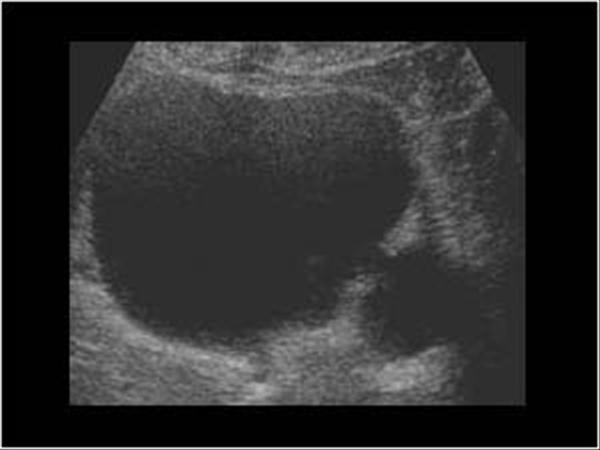

Possible complication of the finding in this bladder U/S?

Infection due to urinary stasis

(Evagination of bladder wall = diverticulum)